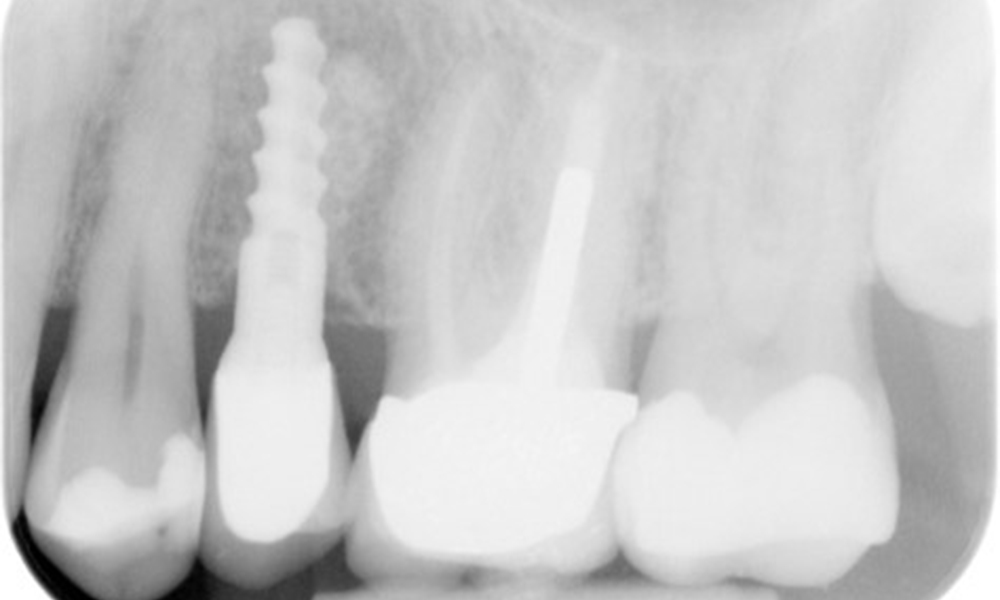

The X-ray image shows the bone loss

The X-ray images show the bone loss.

X-ray images (or bitewing X-rays) taken on: 18/02/2021

X-ray images (or bitewing X-rays)